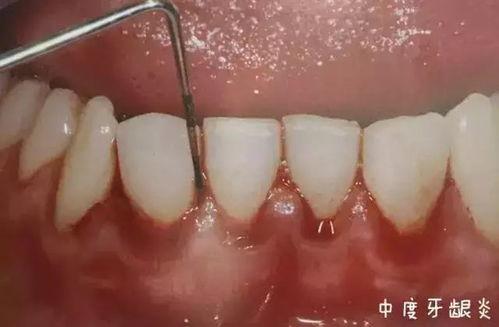

1. 牙龈出血:这是牙龈炎症的早期表现,也是牙龈表皮脱落的前兆。当你刷牙或者吃硬物时,牙龈会出血。

2. 牙龈红肿:牙龈炎症会导致牙龈红肿,触摸时会有疼痛感。

3. 牙龈萎缩:随着炎症的加重,牙龈会逐渐萎缩,导致牙龈与牙齿分离。

4. 牙龈表皮脱落:这是牙龈炎症的严重表现,牙龈表面会出现白色或黄色的皮屑,严重时甚至会出现溃疡。